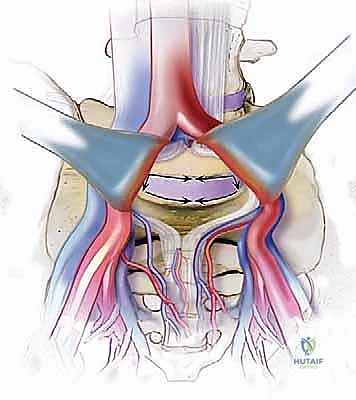

يقوم الجراح بإجراء شق صغير (عادة من 3 إلى 5 بوصات) في أسفل البطن. يتم إزاحة عضلات البطن بلطف جانباً دون قطعها (في الغالب).

الخطوة 2: التعامل مع الأوعية الدموية (Vascular Mobilization)

هذه هي الخطوة الأكثر دقة. أمام العمود الفقري القطني توجد الأوعية الدموية الكبرى في الجسم (الشريان الأورطي والوريد الأجوف السفلي وتفرعاتهما). باستخدام أدوات دقيقة ورؤية مكبرة، يتم تحريك هذه الأوعية بلطف شديد لحمايتها وكشف القرص الفقري المستهدف (غالباً L4-L5 أو L5-S1).

الخطوة 3: استئصال القرص (Discectomy)

بمجرد كشف القرص، يقوم الأستاذ الدكتور محمد هطيف بإزالة المادة الغضروفية التالفة بالكامل. يتم تنظيف الصفائح النهائية للفقرات (Endplates) العلوية والسفلية بعناية فائقة للوصول إلى العظم النازف، وهي خطوة حاسمة لضمان نمو العظم الجديد والتحامه.